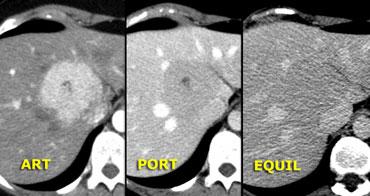

Bên trái là hình ảnh u máu điển hình.

Ngấm thuốc trong pha động mạch gần như đồng tỷ trọng với động mạch chủ, và khi thuốc cản quang khuếch tán về phía trung tâm tổn thương, mức độ ngấm thuốc giảm dần, và trong pha muộn vẫn còn tăng tỷ trọng so với các khoang mạch máu.